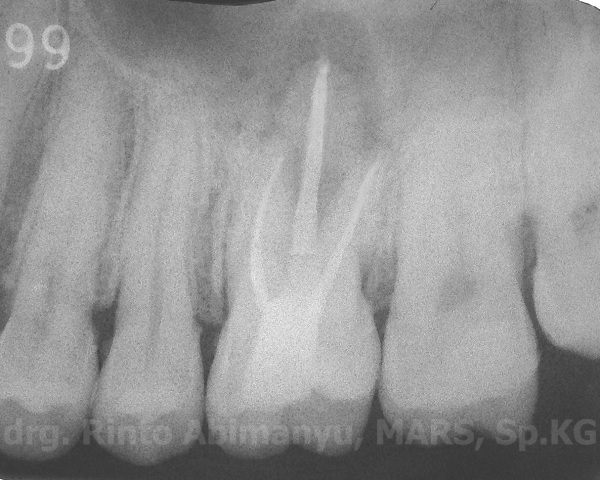

Dari foto ronsen terlihat tambalan yang hampir mengenai kamar pulpa dan lesi radiolusen yang luas pada akar palatal…. Dari hasil pemeriksaan klinis dan radiografis sudah bisa dipastikan bahwa gigi ini nekrosis, dan perjalanan infeksinya sudah sampai membentuk abses…

Ini penampakan gigi 26 setelah preparasi saluran akar…

Berikut penampakan setelah dilakukan pengisian…

Hasil ronsen nya pun menunjukkan pengisian yang hermetis dan adaptasi tambalan yang baik…